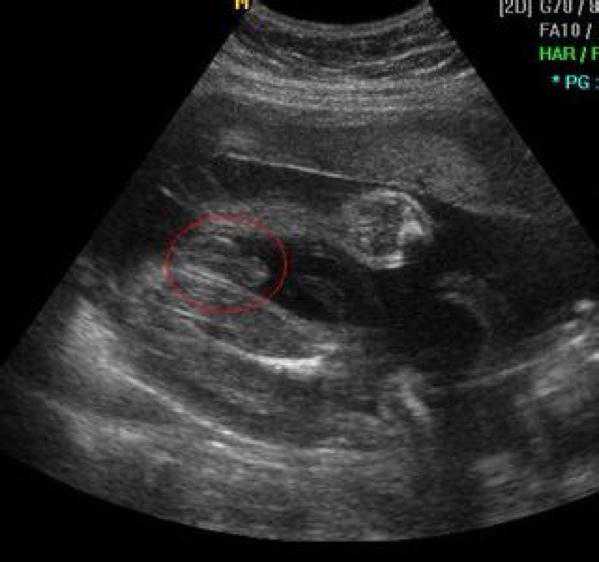

最后来个可爱的四维照!

有没有觉可爱到爆!